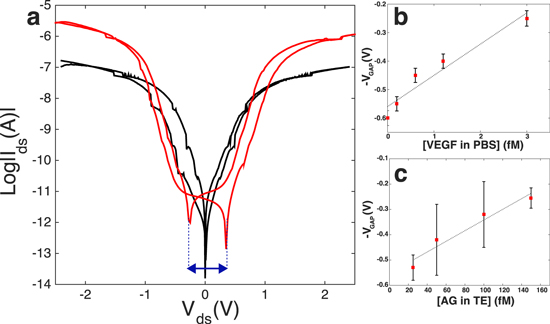

Characterization of the biofunctionalization process was performed both by observation with SEM and fluorescence imaging. In figure 2 we report the SEM micrographs of one of the fabricated devices (a) before and (b) after surface biomodification. From figure 2(b) it is clearly evident the formation of a biolayer of AB around the nanostructure. Figure 3(a) shows the semi-logarithmic Ids–Vds curve of one fabricated SiNW device. The Ids–Vds curve presents a hysteresis loop that is pinched at  V for devices with bare surfaces (black curve), and is clear mark of a memristive system [10, 11]. Once functionalized with ABs, the I–V curve of the sensor changes (figure 3(a)); a non-zero current is now observed when the voltage is swept back to zero (red curve), which is different from the initial condition of zero current at zero voltage. The pinched loop is lost and replaced by a voltage gap defined by the difference in voltage between the crossing points of the forward and backward Vds curves with the x-axis. When the sensor is exposed to a solution of specific AG, then washed, dried and measured, a shrinking of the voltage gap is clearly visible. This shrinking is dependent on the concentration of the target molecule, as demonstrated by the calibration curve reported in figures 3(b) and (c). Details on the sensing protocol and the electrical acquisition are reported in section I of the SI. It is important to observe that all the measurements are performed in air, under fixed relative humidity conditions [9] that are kept constant by continuous monitoring in a sealed measurement chamber. This set-up avoids contamination and creates stable conditions for repeatability of the experiment. Note that a number of control experiments are performed with the aim of defining the electrical noise introduced by interfering species. For example, the effect of silanization on the voltage gap variation has been acquired and, by comparison, estimated to be negligible with respect to the voltage gap modification measured after AB functionalization and AG uptake. Testing the effect of the blocking step with gelatin would lead to further information on the charge-based behavior of the AB–AG complex. In figure 3(b) the experiment consisted of in-air sensing, with the voltage gap technique, of the cancer marker vascular endothelial growth factor (VEGF), diluted in PBS solution in very low concentrations (fM). Figure 3(c) reports the most recent results achieved in the detection of small amount (75–150 fM) of rabbit AG dispersed in the more challenging environment of a breast TE. The TE is prepared directly from patient biopsies (see the SI for details on the TE preparation process), with formation of a cell lysate that is then used for sensing once diluted in PBS, without any kind of filtering. The final concentration of the detected AG in the TE is extremely challenging considering the 100 000 fold mass excess of nonspecific tumor proteins. Data illustrated in figure 3(c) demonstrate the capability of this novel technique in profiling very small concentration changes after interaction with a real biological sample. To the best of our knowledge, the literature reports very few works on immuno-biosensors based on SiNWs capable of measuring femtomoles of AGs in a complex sample such as a TE. Most of the high-sensitive results have been achieved with SiNW-FETs for the detection of RNA with DNA based probes [28]. Very recently, SiNW-FET based in-air immuno-biosensors have been demonstrated as a valid candidate for the highly sensitive detection of cancer markers in real patient samples [23]. However, these results are based on the electrical measurement of the conductance according to the state-of-the-art ISFET technology. In this article we intend to report, for the very first time, an interesting alternative to the femtomolar detection in real breast TEs with memristive immuno-based SiNWs. Memristive nanowires have already been proposed for memory and computation applications but never as ultra-highly sensitive biosensors for detection in breast tumor tissues.

V for devices with bare surfaces (black curve), and is clear mark of a memristive system [10, 11]. Once functionalized with ABs, the I–V curve of the sensor changes (figure 3(a)); a non-zero current is now observed when the voltage is swept back to zero (red curve), which is different from the initial condition of zero current at zero voltage. The pinched loop is lost and replaced by a voltage gap defined by the difference in voltage between the crossing points of the forward and backward Vds curves with the x-axis. When the sensor is exposed to a solution of specific AG, then washed, dried and measured, a shrinking of the voltage gap is clearly visible. This shrinking is dependent on the concentration of the target molecule, as demonstrated by the calibration curve reported in figures 3(b) and (c). Details on the sensing protocol and the electrical acquisition are reported in section I of the SI. It is important to observe that all the measurements are performed in air, under fixed relative humidity conditions [9] that are kept constant by continuous monitoring in a sealed measurement chamber. This set-up avoids contamination and creates stable conditions for repeatability of the experiment. Note that a number of control experiments are performed with the aim of defining the electrical noise introduced by interfering species. For example, the effect of silanization on the voltage gap variation has been acquired and, by comparison, estimated to be negligible with respect to the voltage gap modification measured after AB functionalization and AG uptake. Testing the effect of the blocking step with gelatin would lead to further information on the charge-based behavior of the AB–AG complex. In figure 3(b) the experiment consisted of in-air sensing, with the voltage gap technique, of the cancer marker vascular endothelial growth factor (VEGF), diluted in PBS solution in very low concentrations (fM). Figure 3(c) reports the most recent results achieved in the detection of small amount (75–150 fM) of rabbit AG dispersed in the more challenging environment of a breast TE. The TE is prepared directly from patient biopsies (see the SI for details on the TE preparation process), with formation of a cell lysate that is then used for sensing once diluted in PBS, without any kind of filtering. The final concentration of the detected AG in the TE is extremely challenging considering the 100 000 fold mass excess of nonspecific tumor proteins. Data illustrated in figure 3(c) demonstrate the capability of this novel technique in profiling very small concentration changes after interaction with a real biological sample. To the best of our knowledge, the literature reports very few works on immuno-biosensors based on SiNWs capable of measuring femtomoles of AGs in a complex sample such as a TE. Most of the high-sensitive results have been achieved with SiNW-FETs for the detection of RNA with DNA based probes [28]. Very recently, SiNW-FET based in-air immuno-biosensors have been demonstrated as a valid candidate for the highly sensitive detection of cancer markers in real patient samples [23]. However, these results are based on the electrical measurement of the conductance according to the state-of-the-art ISFET technology. In this article we intend to report, for the very first time, an interesting alternative to the femtomolar detection in real breast TEs with memristive immuno-based SiNWs. Memristive nanowires have already been proposed for memory and computation applications but never as ultra-highly sensitive biosensors for detection in breast tumor tissues.

Standard image High-resolution imageFigure 3. The voltage gap detection approach. (a) The fully pinched hysteresis loop of a just fabricated SiNW (black curve) is lost when its surface is modified with AB (red curve). The adsorption of charged proteins is demonstrated by the augmented current peak and the appearance of a voltage gap. The voltage gap is a parameter of sensing; it decreases as a function of femtomolar concentrations of vascular factors in PBS (b), and as a result of the sensing of AG in the more challenging environment of a breast TE (c). The reported error bars stand for the standard deviation of multiple measures of the same sensor (b), and the standard deviation of the voltage gap acquisitions are related to three similar devices under the same exposure conditions (c).